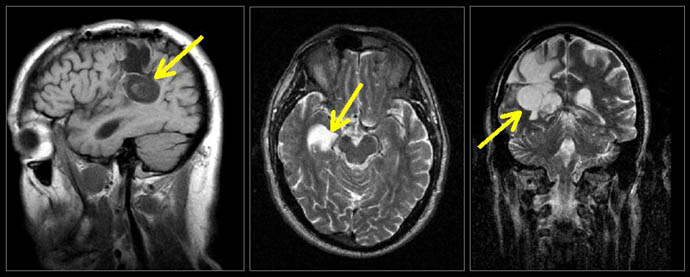

These signal amplitude differences enabled cancer tissues (Figures 11-13) and other tissues to be visualized in MRI images because the signal differences generate the needed brightness differences "PIXEL CONTRAST (IMAGE DETAIL)" in the picture elements (pixels) needed to visualize detail in the MRI image. The CONTRAST

in pixel brightness, "PIXEL

CONTRAST (IMAGE DETAIL)", allows the cancer

pixels in the image to be distinguished from the surrounding

normal pixels. (Figs 11-13) NO SIGNAL

Figure 11.

T2 MRI visualization of a tumor of the brain made possible

by the discovery

of Damadian of the abnormal T2 (and T1) MR (NMR) relaxations

of cancerous tissue.

Figure 14 is an axial (cross-sectional) image of the brain showing a tumor of the cerebellum (white areas) in the midline. Figure 14c is a magnified image showing the picture elements or "pixels" (small squares) that make up the image. The cerebellar tumor as it would appear (D) with no MR signal differences. Figure D is the same image as B but where all MR signal differences were eliminated and all the MR pixels therefore had the same pixel brightness. The absence of the MR signal differences between cancer and normal tissue discovered by Damadian gives the MR image pixels equal brightness and the tumor becomes Invisible. |

Were the amplitudes of the NMR signals (fig.9) used to set the brightness of each MRI image pixel the same for all tissues (and prior to Dr. Damadian's discovery such NMR tissue signal differences were not known to exist) the brightness of each image pixel would be the same. The MR image would be a blank.

The NMR signal differences discovered by Damadian (Figs 6,9,tables 1 & 2) vary the brightness of the pixels that make up the image (Figs. 6,9). The signal differences of diseased and normal tissues generate the large differences in pixel brightness that enable all diseased tissues (cancerous as well as non-cancerous) to be exquisitely visualized (fig.3b,10,11-13) by the MRI image. Additionally the exceptional NMR signal differences among the normal tissues discovered by Damadian give rise to the extraordinary detail of normal anatomy visualized by MRI (figs. 7,8)